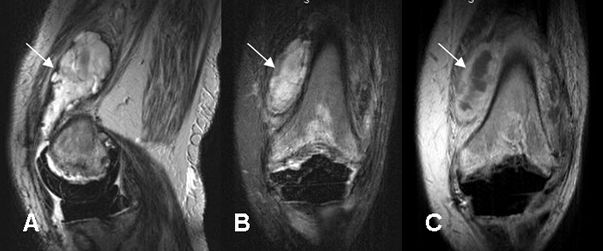

Fig 25. Absceso.

A: RM sagital en T2, B: RM coronal en STIR y C: RM coronal en T1 con contraste. Igual paciente de la figura 18, con prótesis metálicas hipointensas en todas las secuencias. Colección en la parte anteromedial del muslo, de señal heterogénea y predominio hiperintenso en T2 y STIR, cuyos bordes realzan con el contraste, por la formación de absceso.